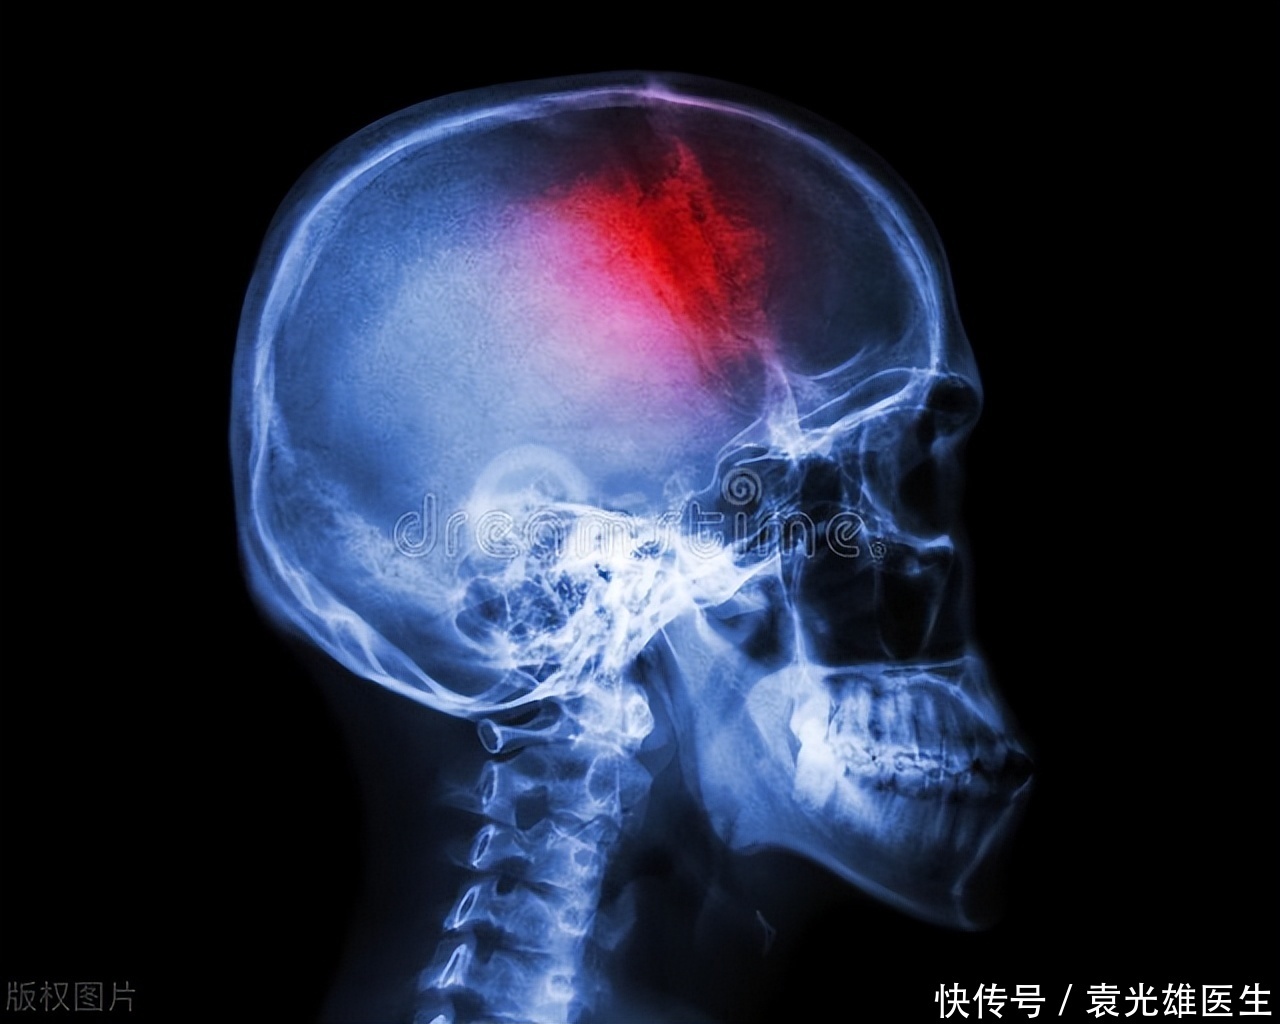

如何避免高血压并发脑出血?做好7点预防,有利血管健康